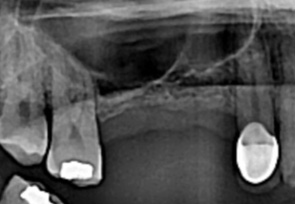

before

-

after